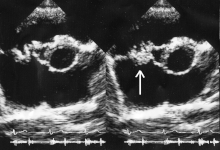

Vegetation on the tricuspid valve by echocardiography. Arrow denotes the vegetation.

In general, the Duke criteria should be fulfilled in order to establish the diagnosis of endocarditis.[5][31] Although the Duke criteria are widely used, they have significant limitations.[5] For example, the sensitivity of the Duke criteria for detecting infective endocarditis decreases when prosthetic heart valves are present.[5]